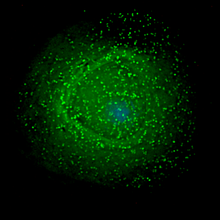

Immune reconstitution inflammatory syndrome is seen in some HIV-infected patients soon after initiation of antiretroviral therapy. The syndrome can “unmask” dormant opportunistic infections or aggravate existing infections.